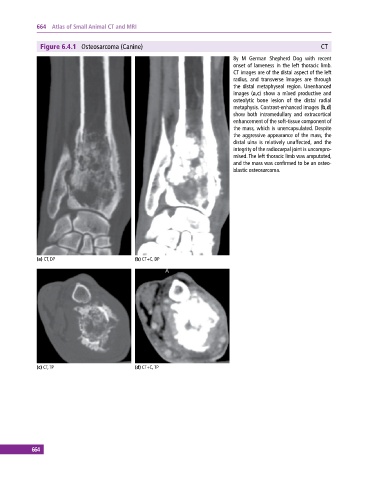

Figure 6.4.1 Osteosarcoma (Canine) CT

8y M German Shepherd Dog with recent

onset of lameness in the left thoracic limb.

CT images are of the distal aspect of the left

radius, and transverse images are through

the distal metaphyseal region. Unenhanced

images (a,c) show a mixed productive and

osteolytic bone lesion of the distal radial

metaphysis. Contrast‐enhanced images (b,d)

show both intramedullary and extracortical

enhancement of the soft‐tissue component of

the mass, which is unencapsulated. Despite

the aggressive appearance of the mass, the

distal ulna is relatively unaffected, and the

integrity of the radiocarpal joint is uncompro-

mised. The left thoracic limb was amputated,

and the mass was confirmed to be an osteo-

blastic osteosarcoma.

(a) CT, DP (b) CT+C, DP

(c) CT, TP (d) CT+C, TP